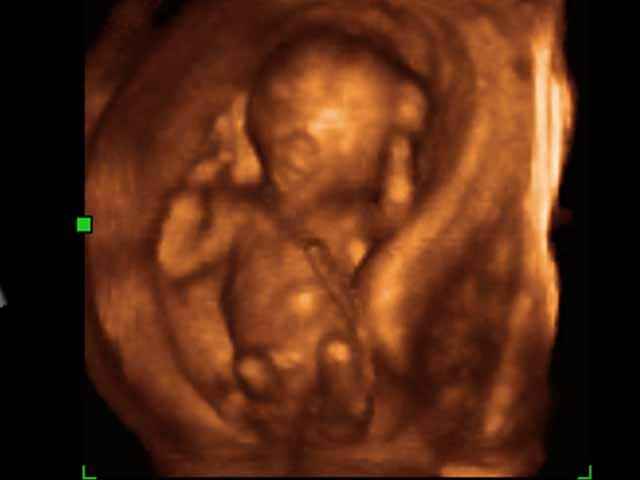

- 3D second trimestre échographie Photos de numérisation